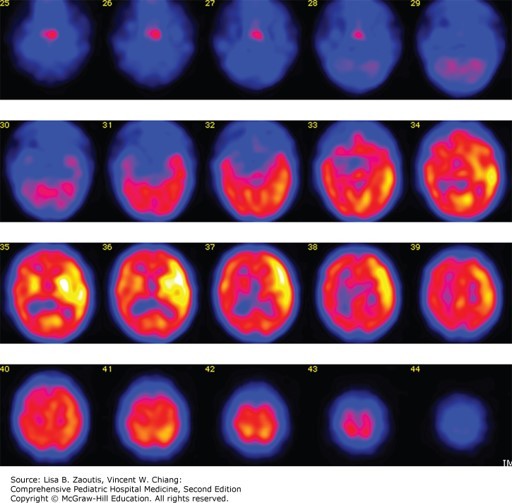

Photo: Zaoutis LB, Chiang VW. Comprehensive Pediatric Hospital Medicine, 2e; 2017